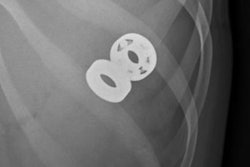

![]() |

| X-ray of a 2-year-old male after swallowing a battery from a Christmas ornament. Image shows the battery (indicated by arrow) has moved into the colon. Image courtesy of Children's Hospital Boston. |

Eighty-six percent of the patients had diagnostic imaging procedures, the majority of which were x-rays (82.8%). Two patients had CT examinations. Thirty-one patients had more than one diagnostic imaging procedure, according to lead author Dr. Amir Kimia, a pediatric emergency medicine specialist.